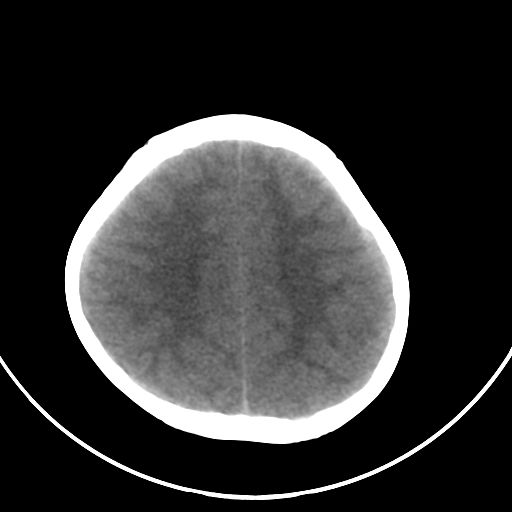

以下是引用zjzjr在2008-7-27 9:56:00的发言:[br]考虑髓母细胞瘤伴梗阻性脑积水.建议增强或mri

以下是引用子十在2008-7-27 9:53:00的发言:[br]考虑髓母细胞瘤